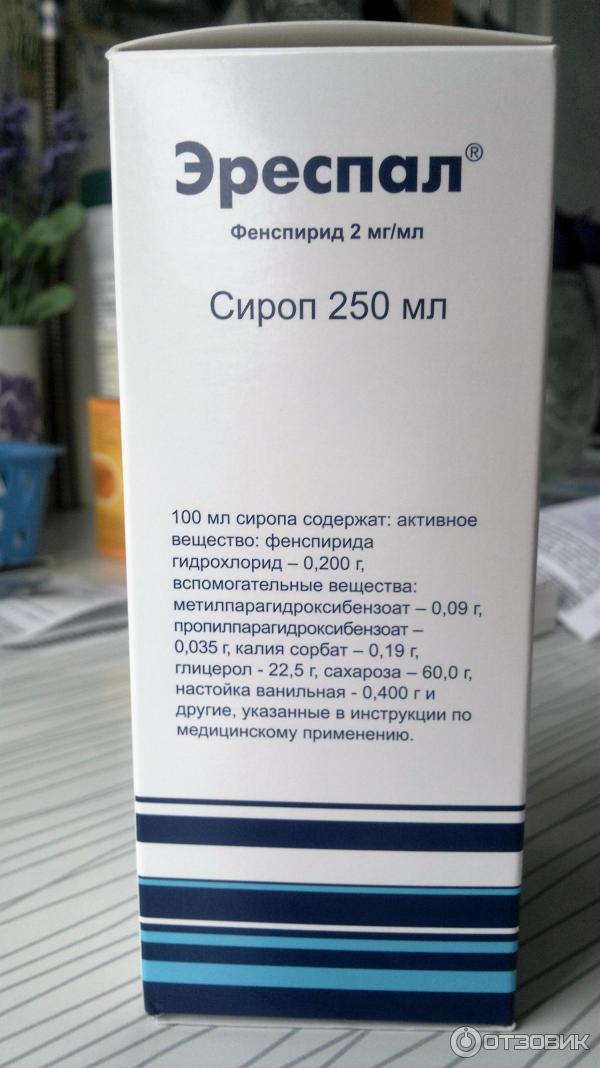

Эреспал детям